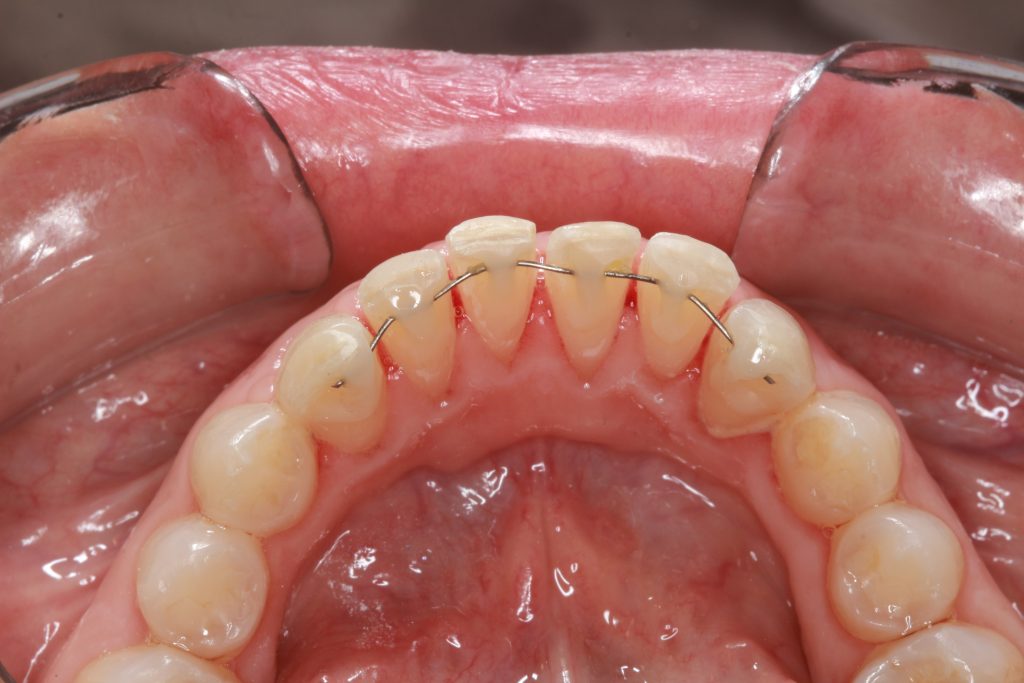

Los 4 incisivos inferiores los tenía ligeramente vestibularizados y apiñados para lo cual se procedió a realizar la técnica de stripping en los espacios interproximales entre canino y canino y luego se instaló el alambre de niti 014 desde la pieza 3.3 hasta la pieza 4.3 pegado con resina directamente sobre el esmalte de la cara lingual del diente.

Previo al inicio de tratamiento

Primer control (a los 15 días)